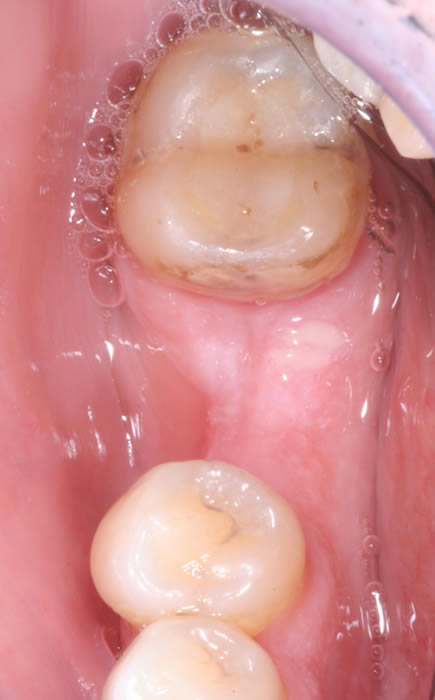

More back teeth replaced by dental implants

Case Three (2 images)

Case Four (4 images)

Case Five (4 images)

Case Six (8 images)

Case Seven (4 images)